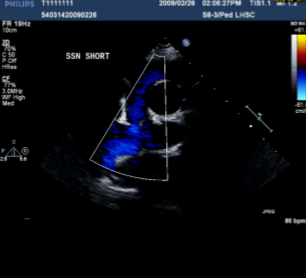

Describe the findings of this image.

Anastomosis between SVC and RPA → BDG shunt